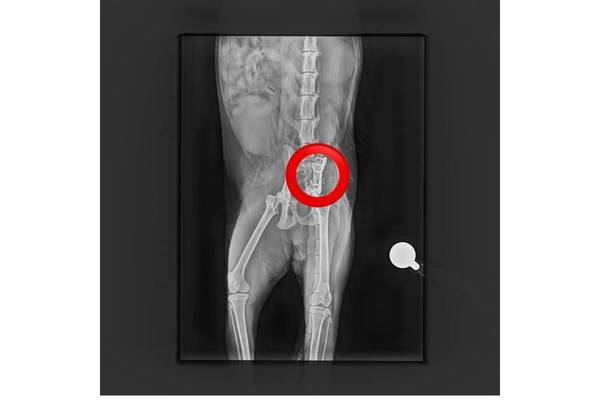

Kürzlich hat der Tierschutzhof Pfotenhilfe einen schwer verletzten Kater aufgenommen, der in Mondsee (OÖ) gefunden wurde und ihn unverzüglich zum auf orthopädische Chirurgie spezialisierten Tierarzt Mag. Daniel Eschlböck in Alkoven (OÖ) gebracht. Dieser hat auf den Röntgenbildern multiple Beckenbrüche festgestellt und bereits eine Seite operiert, jetzt folgt die zweite Operation. Die Verletzungen deuten auf einen Autounfall oder Sturz hin. Der Kater ist natürlich stationär bei ihm untergebracht.